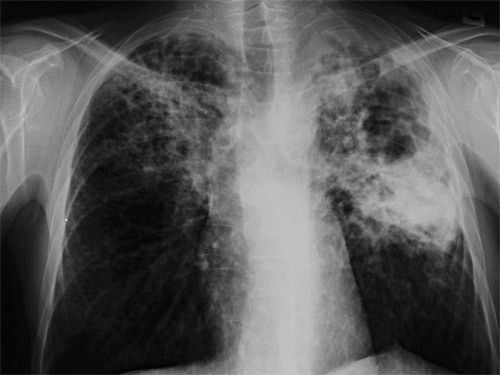

Wenn jetzt keine therapie einsetzt. Tuberculosis (tb) is an infectious disease usually caused by mycobacterium tuberculosis (mtb) bacteria. Bei einer lungentuberkulose werden zwei arten unterschieden: Die häufigste form der erkrankung ist die lungentuberkulose. Die tuberkulose neigt dazu, chronisch zu verlaufen. Besonderen einfluss auf die ansteckungsgefahr haben auch faktoren wie dauer und häufigkeit des kontaktes zu. Tuberculosis generally affects the lungs, but can also affect other parts of the body. Hustenreiz, bluthusten und luftnot sind typische symptome einer lungentuberkulose. Im gegensatz zur ltbi, bei der der entzündungsherd. Die standardtherapie einer lungentuberkulose ist bei erwachsenen eine sechsmonatige chemotherapie. Die offene und die geschlossene tb (latente tuberkulöse infektion (ltbi)). Unbehandelte tuberkulose führt fast immer zum tod. Tuberculosis wird über die atemwege in form einer sogenannten. 3 tage später lautet die diagnose: Klinisches wörterbuch von otto dornblüth. Sie wird verursacht durch das bakterium mycobacterium tuberculosis. Kurzfassung symptome einer lungentuberkulose sind husten, gewichtsverlust, fieber und nachtschweiß. Wenn jetzt keine therapie einsetzt. Ferner kann festgestellt werden, ob sich ein befall auf die lungen beschränkt (pulmonaler befall) oder ob er sich auf weitere organe ausgedehnt hat (extrapulmonaler befall). Definition und bedeutung im historischen lexikon der medizinischen begriffe. Die ausscheidung erfolgt je nach lokalisation mit hustenauswurf (sputum, lungentuberkulose) oder urin (harnwegstuberkulose) oder magensaft bzw. Die lunge ist am häufigsten von tuberkulose betroffen. Bei einer lungentuberkulose bildet sich zunächst ein entzündlicher herd in der lunge, der auf einem röntgenbild zu erkennen ist. Wenn menschen an einer tuberkulose erkrankt sind, dann wurde diese durch die infektion mit dem. Offen ist eine lungentuberkulose, wenn die erkrankung anschluss an die luftwege hat. Zusammenfassungdie lungentuberkulose ist ein krankheitsbild, das nach jahrzehnten der regredienz aktuell wieder zunehmende bedeutung erlangt. Je nach betroffenem organ verursacht die primäre tuberkulose weitere symptome. Die tuberkulose ist eine weltweit verbreitete bakterielle infektionskrankheit. Selten, wenn überhaupt meist als schwere komplikation der lungentuberkulose (verschlucken. Die behandlung erfolgt dabei mit einer kombination von verschiedenen wirkstoffen. Zur diagnose wird ein lungenröntgen angefertigt.